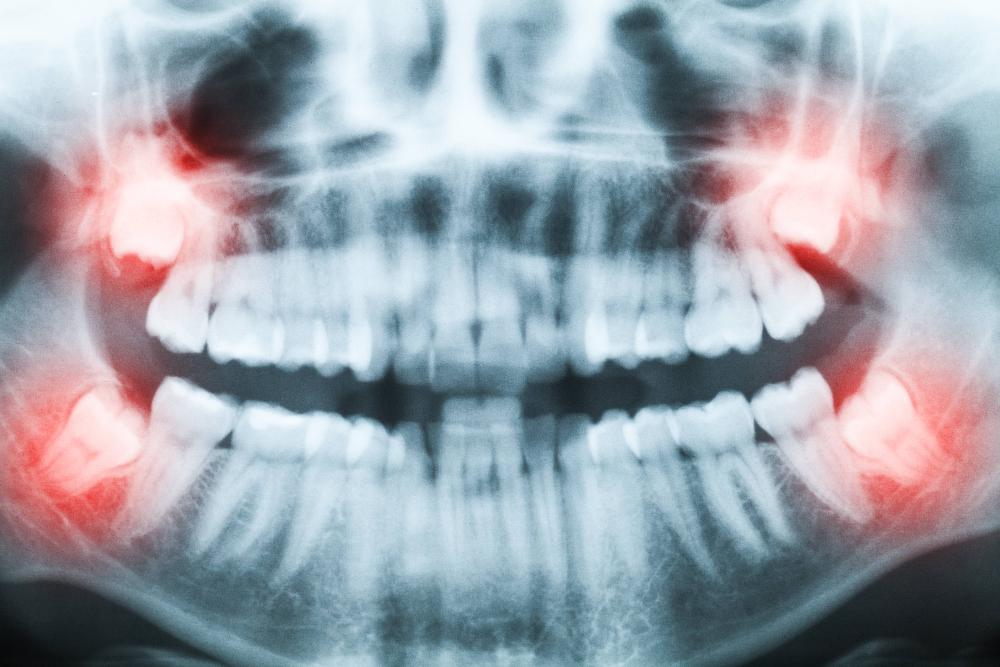

Surgical extractions involve teeth that have not fully erupted from the gums. This often occurs when there is not enough space for the tooth or it is growing in at an angle. This condition, known as impaction, often causes pain and jaw discomfort. Removing your tooth can dramatically improve your comfort and protect your remaining teeth.